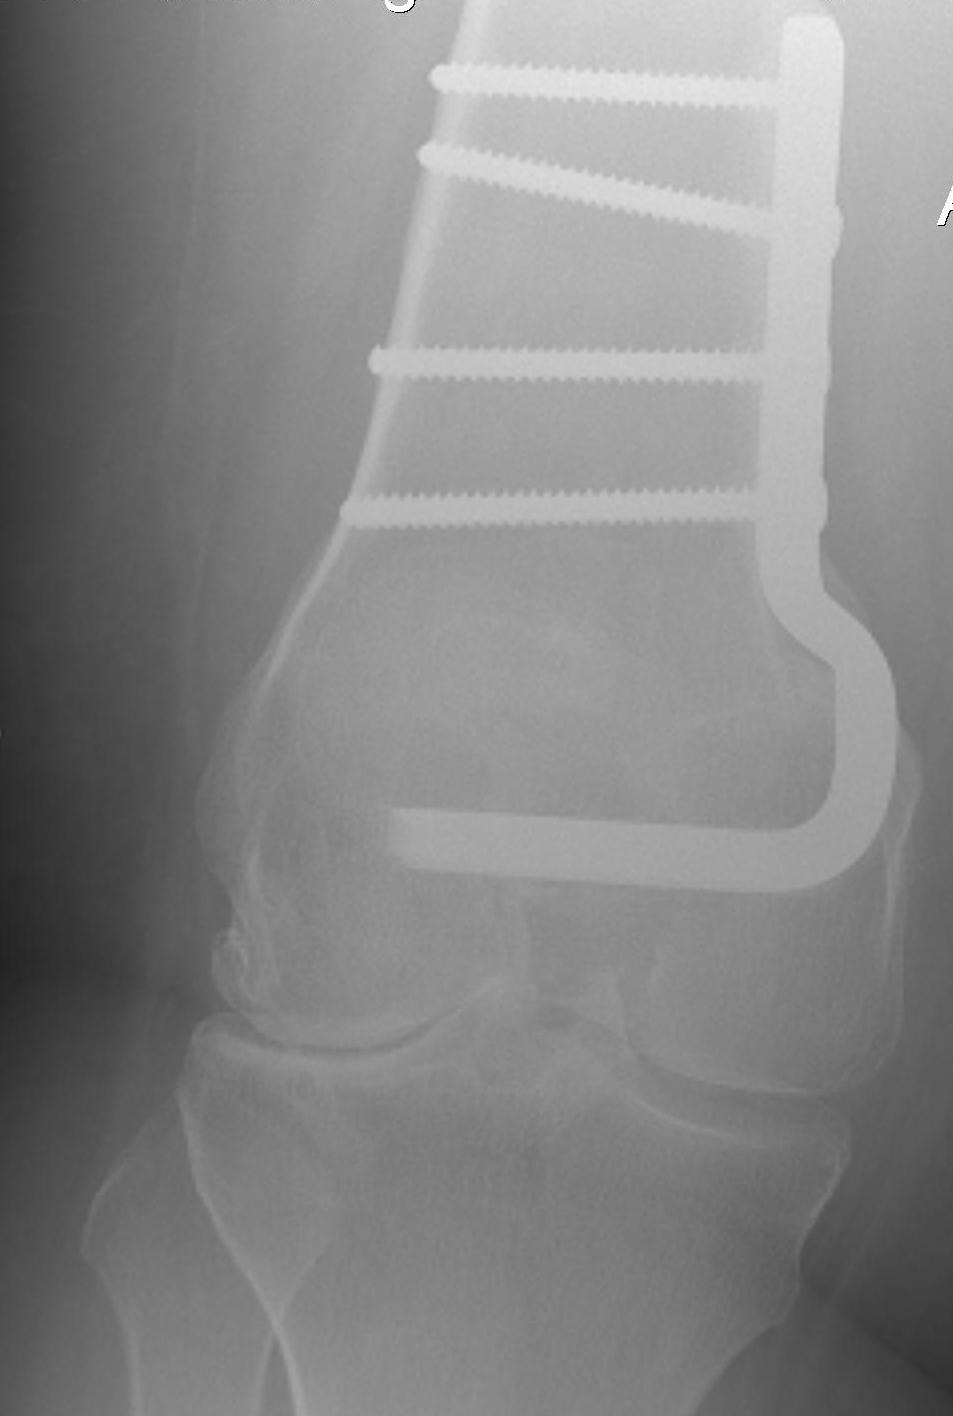

Medial Closing Wedge Osteotomy

Advantages

- lower risk of non union

- better for larger corrections

Distal Femoral Osteotomy MedialDFCO medial closing wedge

Results

Sternheim et al Orthopedics 2011

- 45 CW DFVO for lateral OA

- mean 13 year follow up

- 90% 10 year survival

- 79% 15 year survival

- 22% 10 year survival